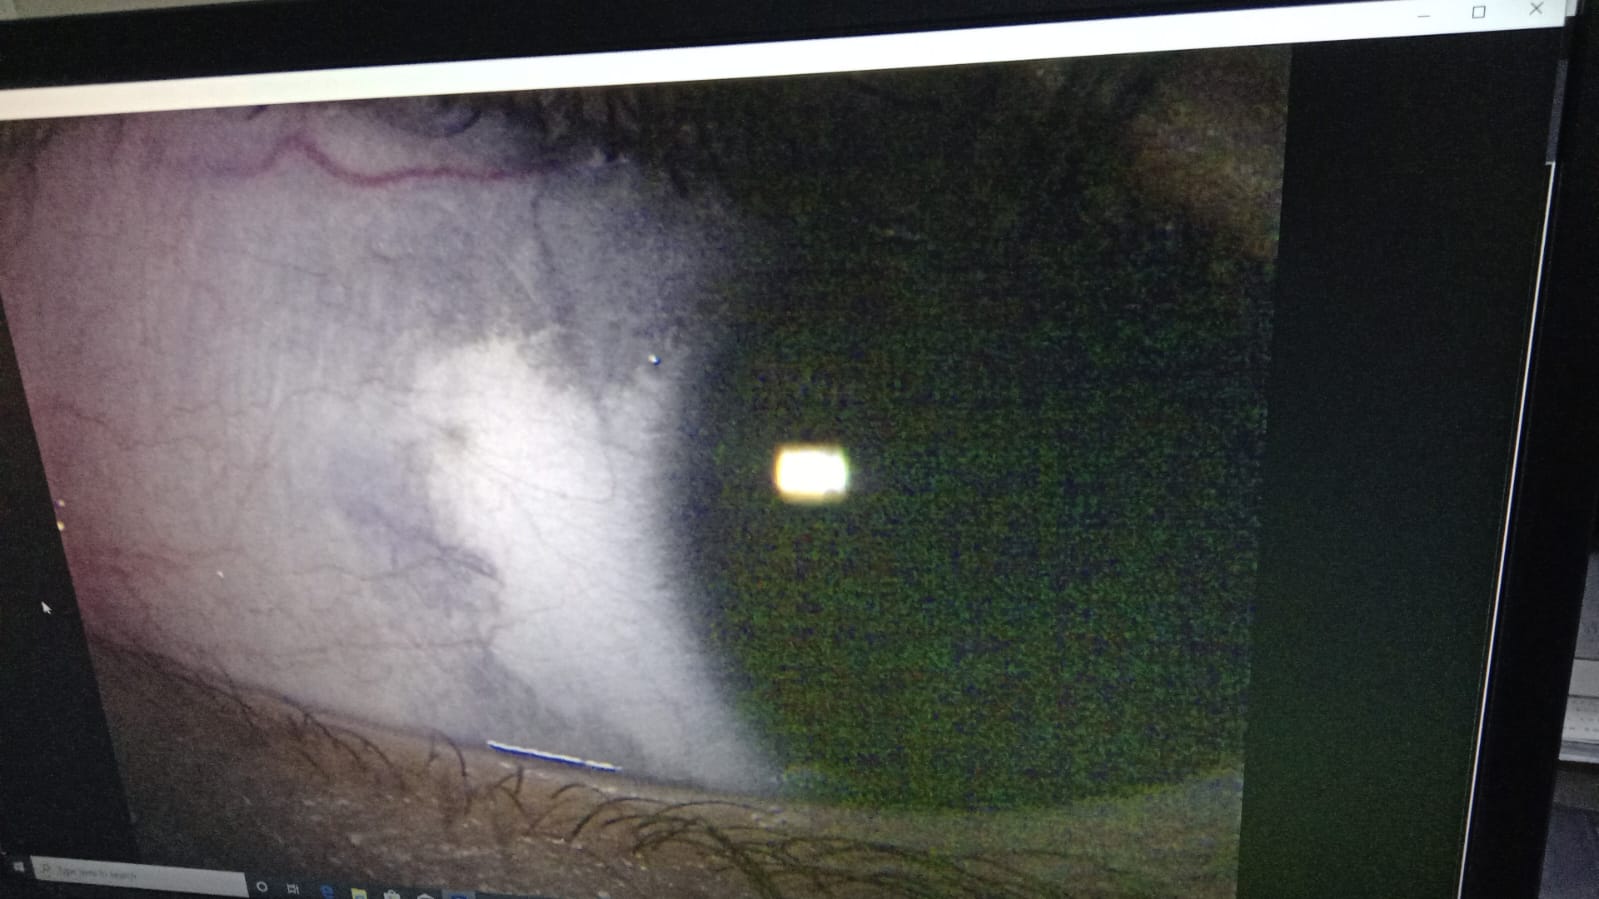

Aslamulikum, please need your expert advice what is it and which doctor we should consult in Peshawar or Islamabad for this pigmentation, it is for my son age of 3 years.

Attach Photo here: